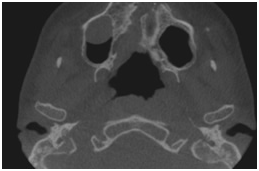

Vista axial Reconstruções 3D